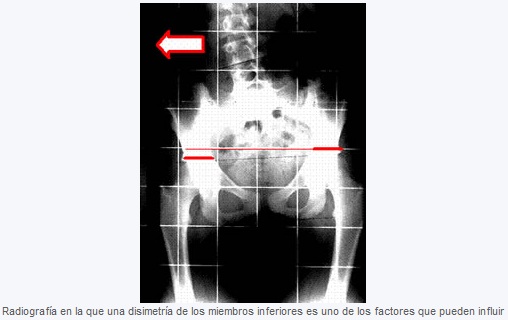

El tratamiento quiropráctico va dirigido a corregir los factores mecánicos en la columna que influyen en la progresión de la escoliosis, algunos tan simples como una dismetría de los miembros inferiores y otros más complejos como la manipulación específica de las vértebras.